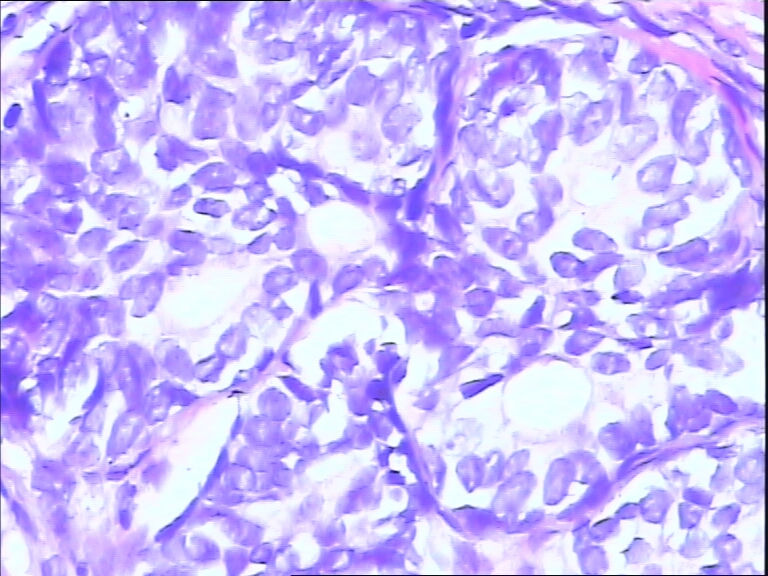

前列腺,请教,急!

图3

前列腺够癌吗?